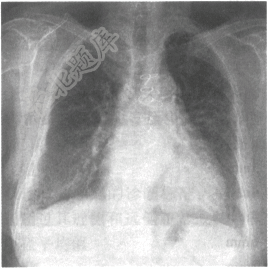

- 单项选择题女性患者,46岁。呼吸困难入院,胸部X线平片如下图,右侧肋膈角区垂直于胸壁内侧面的线状影为

A、Kerley B线

B、胸腔积液

C、盘状肺不张

D、Kerley A线

E、Kerley C线